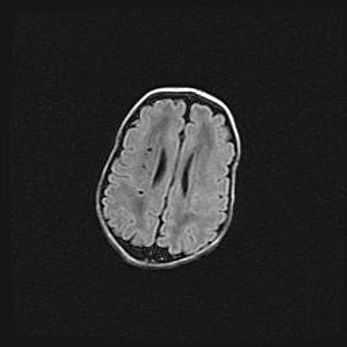

Неполная лизэнцефалия (пахигирия). Открытая гидроцефалия.

Возраст: 17 дней

Вес: 3110 г

Пол: мужской

Окружность головы: 33,5 см

Срок гестации: 35-36 недель

Лизэнцефалия—недоразвитие корковой пластинки и мозговых извилин в результате нарушения миграции нейронов коры. Поверхность мозговых полушарий гладкая. Микроскопически выявляется отсутствие нормальных слоев коры и скопление групп нейронов в подкорковом белом веществе.

Пахигирия—уменьшение числа вторичных извилин. В пораженном полушарии нервные клетки образуют толстый недифференцированный слой с неправильно расположенными нервными волокнами и группами гетеротопных клеток. Нервные клетки незрелые. Белое вещество истончено. При этом нередко аномально развит корково-спинномозговой путь.